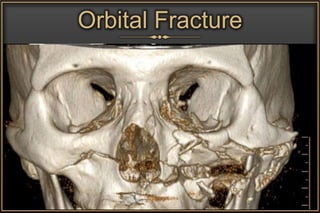

• Orbital Trauma

CT ideal for Bony & Traumatic Manifestations

Orbital Fat

Herniation

Orbital

Emphysema

Orbital Fracture

Water’s View